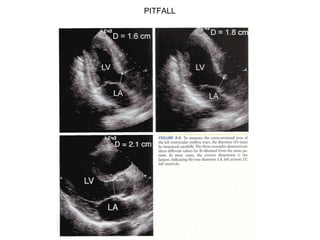

PITFALL

Pitfalls